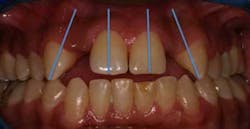

reference lines represent the cephalometric measurement of SN-GoGn. The cranial base reference line

runs through the sella tursica (S) and nasion (N), and the mandibular plane (MP) is created by a line

that bisects the angle of the mandible (Gonion) and connects to the point on the chin called gnathion

(Gn). A “normal” SN-GoGn angle is 32 degrees +/- 5 degrees.